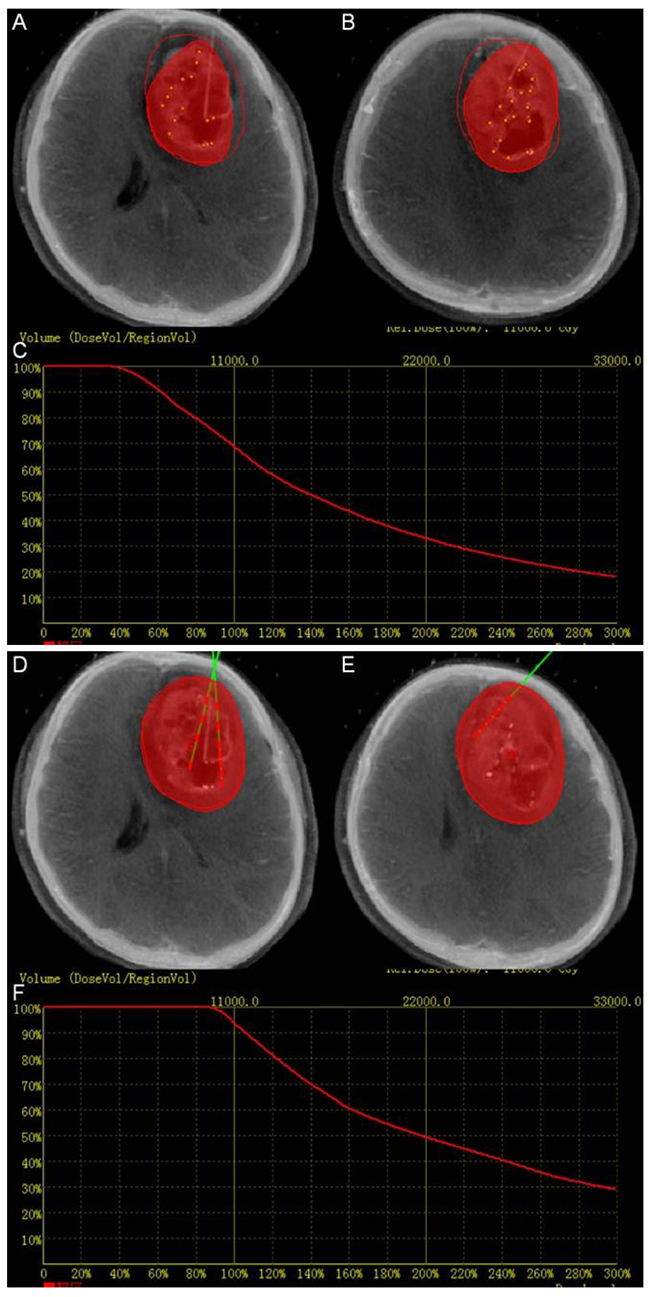

After the insertion of the first catheter, intra-operative CT images were loaded into fusion platform which we designed and were fused to the pre-operative MRI data. The position of catheter can be seen on the screen. Intra-operative CT-MR images fusion provided the comparison of the planning and the operation. If the catheter did not reach the planned position, it can be corrected until the catheter reached the determined target point, at which time the seeds were implanted (Figure 3). Figure 4 summarizes the intra-operative workflow.

Figure 3: Intra-operation. (A), (B), (D) and (E) Fused image can aid to adjust the position of the catheters and seeds in real time. The red perimeter shows the planned treatment area. The red volume shows the treatment achieved at the stage of the implantation. (C) Dose volume histogram of intra-operation. The red curve shows the dose volume histogram of the target. The dose volume showed that the dose did not totally covered the target volume. (F) The final dose volume histogram.